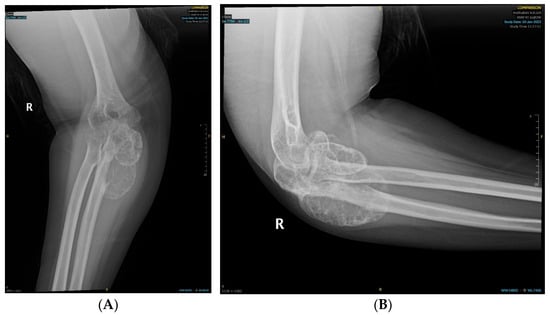

2. Case Presentation